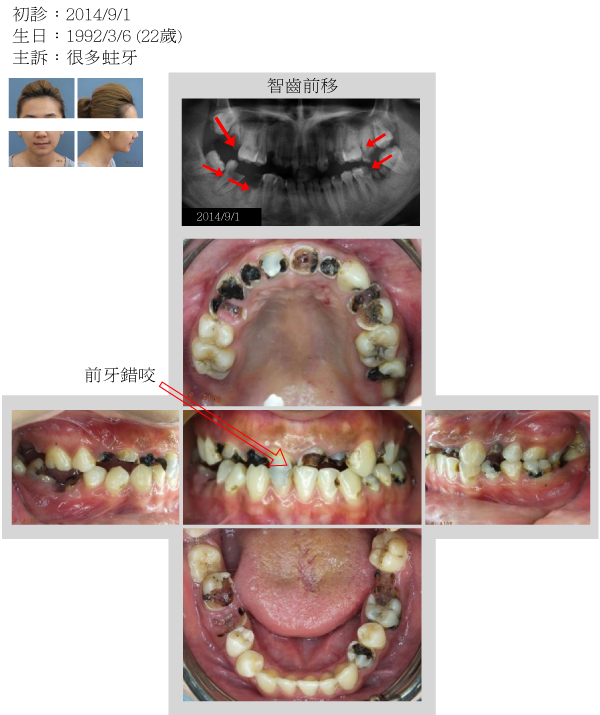

案例一

幸福人生從齒起

健齒養顏 開心樂活

天泉專科團隊協同診治 求精求速